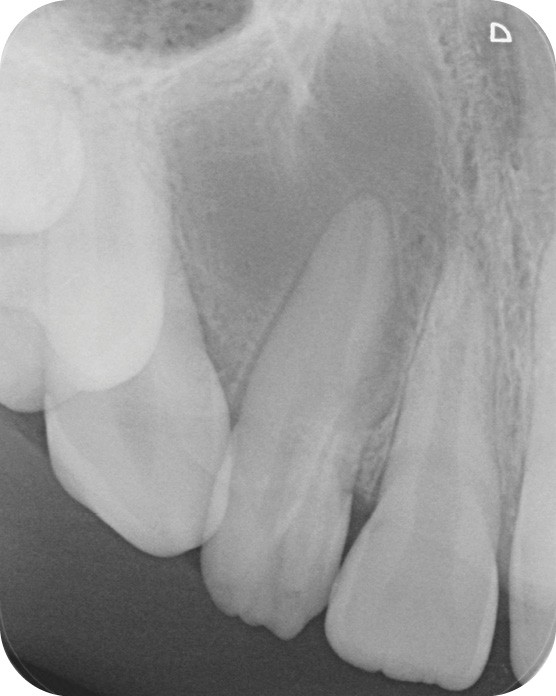

La patiente, âgée de 12 ans, s’est présentée à ma consultation avec une demande du chirurgien de réaliser le traitement endodontique de la 12 avant le curetage sous anesthésie générale. La radiographie périapicale préopératoire a mis en évidence une anatomie complexe. Les tests préopératoires ont montré un sondage parodontal sain, une percussion positive et un test au froid positif. La patiente présentait également une fistule vestibulaire active. Le Cone Beam a mis en évidence la présence d’une dens in dente et d’une lésion imposante ainsi qu’une palatoversion importante de la racine de la 12. La lésion est-elle responsable de ce mouvement dentaire ? (fig. 1, 2 et 3).